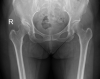

Delayed Femoral Artery Occlusion After Total Hip Arthroplasty via the Posterior Approach: A Single-Case Report From Thailand

Arterial injury after total hip arthroplasty is rare, but the consequences of this complication are serious and potentially life-threatening. Here, we report a case of delayed-onset common femoral artery occlusion after total hip arthroplasty that was performed via the posterior approach at Siriraj Hospital-Thailand's largest university-based national tertiary referral center. Our case was successfully treated with arterial thromboembolectomy. We postulate that anterior retractor placement caused intimal injury to the vessel. Routine monitoring of postoperative vascular pulse is essential. Early detection and prompt vascular surgeon consultation are the important factors for preventing the potentially catastrophic consequences of this complication.